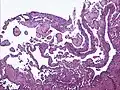

Micrograph of a kaposiform hemangioendothelioma with "glomeruloid" nodules of endothelial cells.

• Kaposiform hemangioendothelioma (also known as "Infantile kaposiform hemangioendothelioma"[3]) is an uncommon vascular tumor, first described by Niedt, Greco, et al. (Hemangioma with Kaposi's sarcoma-like features: report of two cases.(Niedt GW, Greco MA, Wieczorek R, Blanc WA, Knowles DM 2nd. that affects infants and young children, with rare cases having also been reported in adults. Pediatr Pathol. 1989;9(5):567-75.)[2]:596[3]:1782